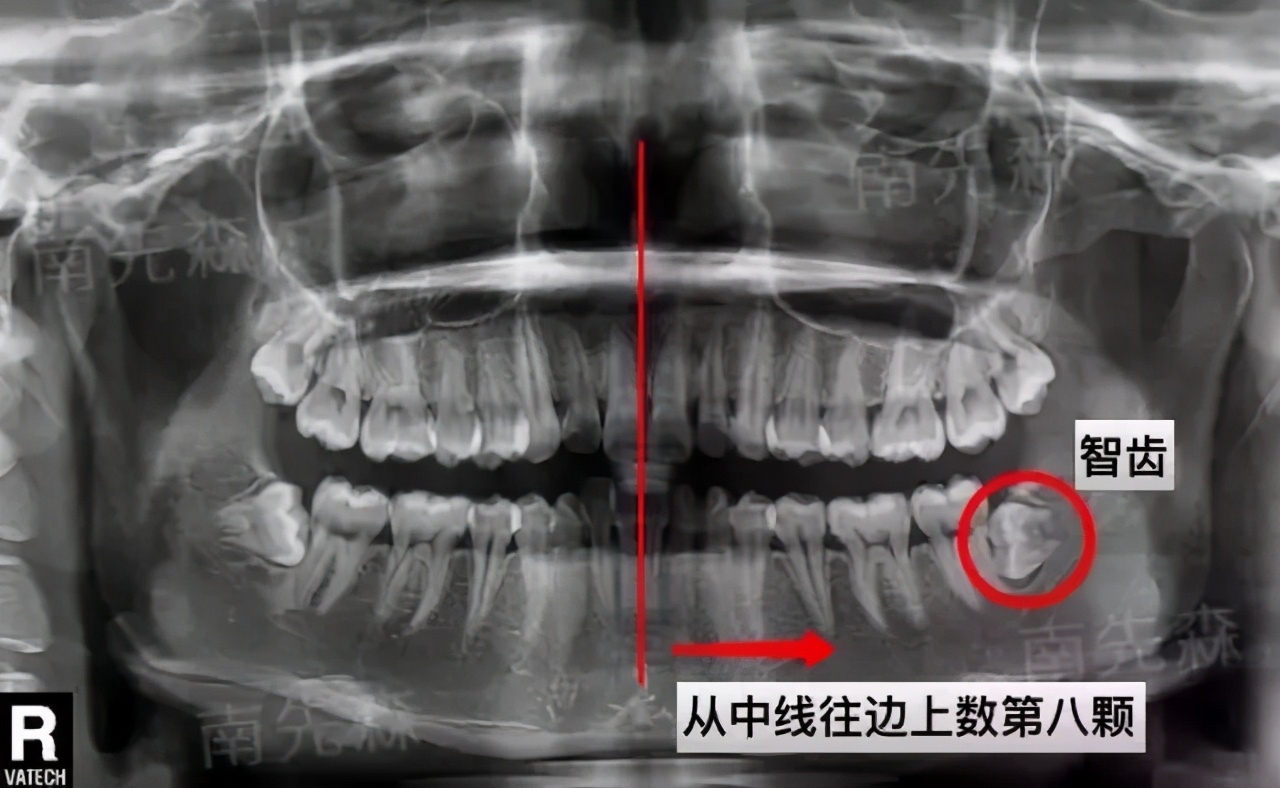

首先你对着镜子,先找到自己的中线位置。在两个门牙中间,就是中线位置。

然后尽可能张大你的嘴,从中线开始往两边数,门牙是第一个,如果你之前没有拔过牙的话, 数到第8颗牙就是智齿 ,如果只有7颗牙,那就是没有长出智齿。

看牙片就能清晰地看到有没有智齿,智齿长的位置怎么样,要不要拔,一切清晰明了。